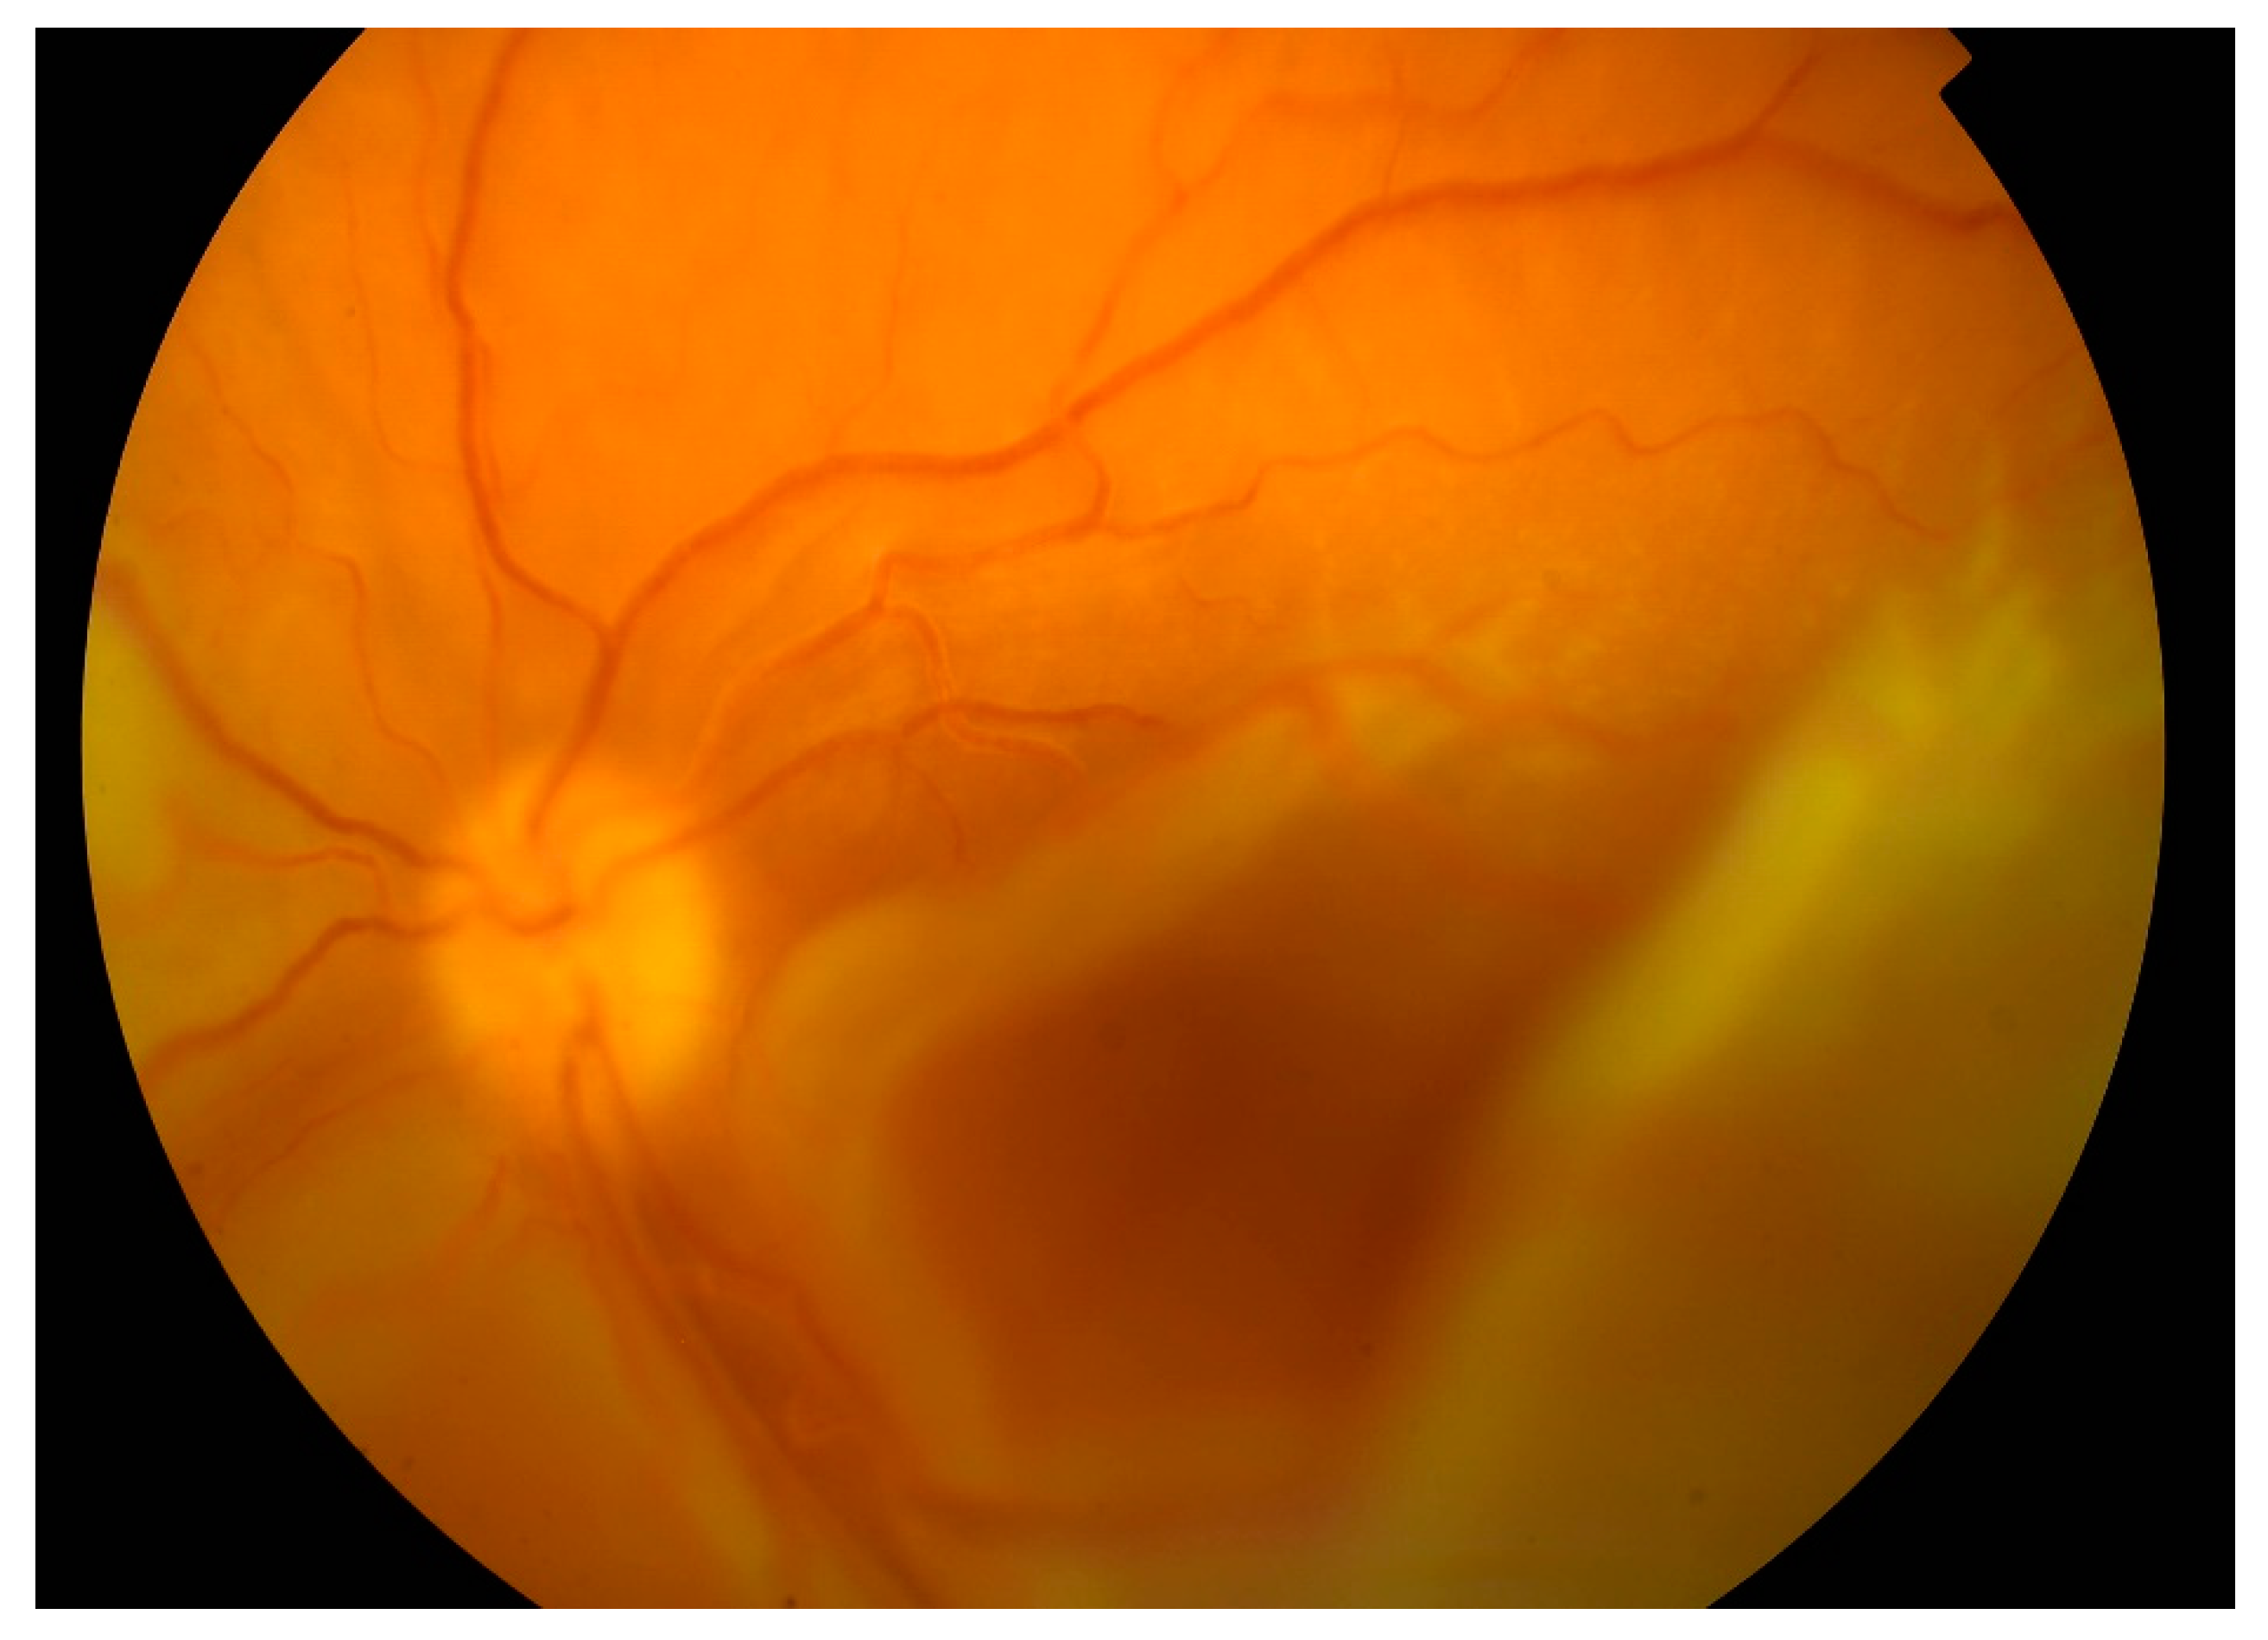

In April 2018, after ending biological treatment, BCVA was unchanged and right eye surgery (23G pars plana vitrectomy with silicone oil 5000 cs tamponade) was performed. One month after surgery BCVA OD improved to 10/200. Central retina was attached on the right eye. From the arcades, flat retinal detachment was present. Left eye worsened with BCVA only light perception, and the retina was completely detached and adhered to the posterior surface of the intraocular lens (Figure 5).

Figure 5. Touch of the detached retina to the posterior surface of the intraocular lens on the left eye.